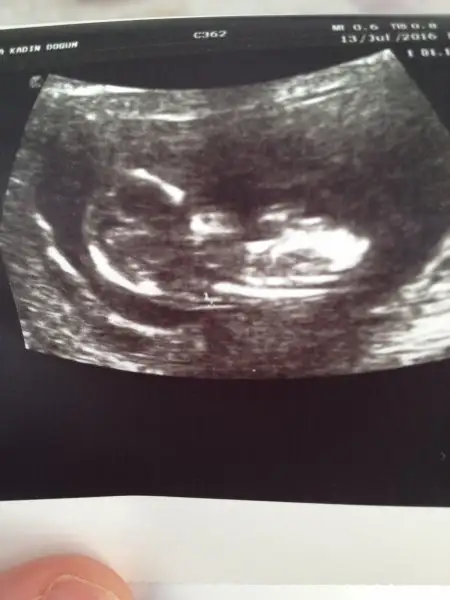

Havalianne__ bu da 7+3 günlük karından ultrason goruntum

7. Hafta karından ultrason görüntüsü. 27 mayıs 2016 son adet tarihi. Eşimin doğum tarihi 12 aralık 1980, benim doğum tarihim 1 eylül 1983...

Tahminin nedir canım?